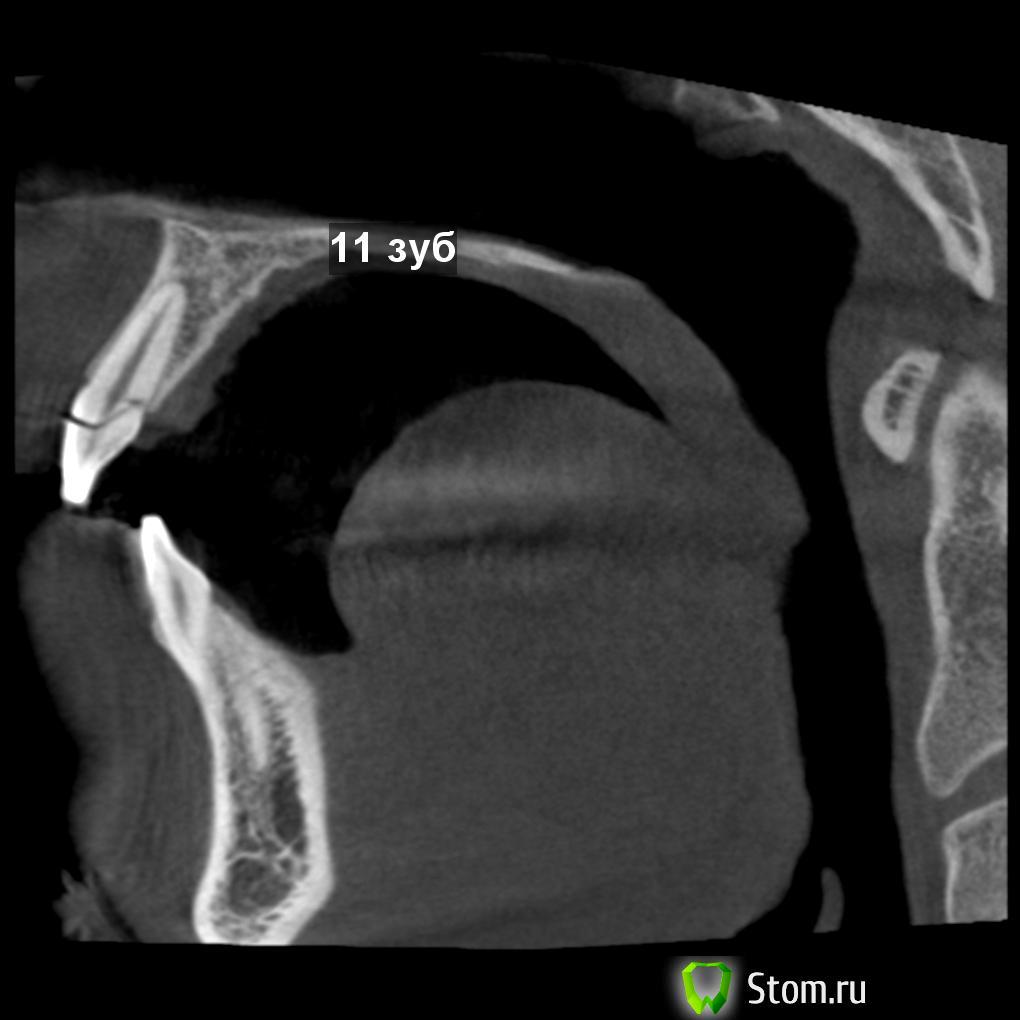

vitaliiPV Опубликовано 11 марта, 2012 Поделиться Опубликовано 11 марта, 2012 Здравствуйте уважаемые доктора. Поделитесь мыслью чтоб Вы сделали .Парню 20 лет , травме несколько дней. Подобных случаев у мене было мало, опыта в таком лечении тоже.Склоняюсь к удалению, хир. удлинение думаю нельзя из за коротких корней.Прислушаюсь ко всем комментариям.Помогите парню вернуть улыбку. Извините за качество фото снимал на телефон. После удаления отломка.12 зуб11 зуб Ссылка на комментарий